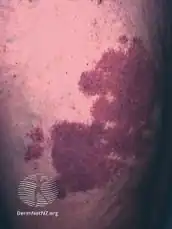

The back of a hand with prominent port-wine staining

SymptomsDark red or purple area of skin with defined borders[1]

Port-wine stain, also known as nevus flammeus, is a birth mark that presents as a dark red or purple area of skin.[1][3] They occur most often on one side of the face or neck;[1][3] though, any part of the body may be involved.[2] They generally have defined borders and over time may become darker and thicken.[2] Complications may include glaucoma.[2]

They generally presents as a dark red or purple area of skin at birth.[1][3] They occur most often on one side of the face or neck;[1][3] though, any part of the body may be involved.[2] They generally have defined borders and over time may become darker and thicken.[2] Complications may include glaucoma.[2]